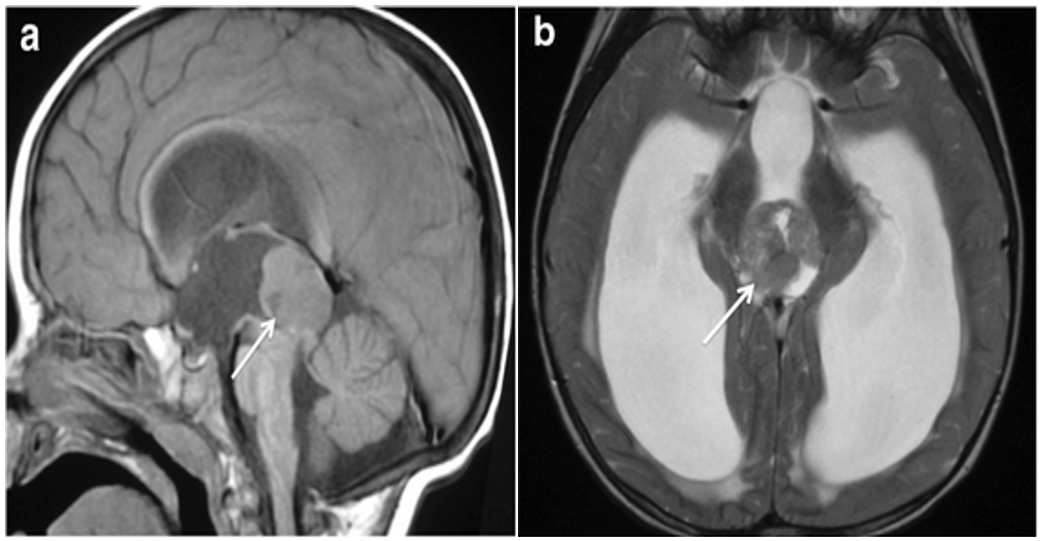

Figure 1. MRI Brain showing tumor arising from the pineal gland (a) Sagittal T1 weighted image (b) Axial T2 weighted image.

A 33-year-old male patient presented with headaches and vomiting for 2 months which led him to a neurological evaluation. His plain head CT scan showed an enlarged pineal gland with smooth margins and several peripheral calcifications. MRI showed a well-defined lesion in the pineal region (14 × 10 mm in the axial plane), which was hyperintense on T1 with diffuse contrast enhancement after gadolinium injection and strongly hypo intense on T2. (Figure 1). MR scan of the spine and CSF cytology resulted in a negative for pathological seeding. The patient also underwent hormonal and tumor markers blood tests and radiological workup with chest and abdominal CT scans, which were all reported as normal. A repeated MRI scan after a short interval confirmed a growing pineal parenchymal tumor, hence patient underwent craniotomy with resection of the tumor.